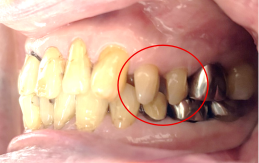

女性 Yさん 60代 (オールセラミック冠)

主訴

以前治療した右下の犬歯が、虫歯になり色が変わってきているので、治したい。

治療内容

根管治療をし、オールセラミック冠を被せました。

所感

神経が取り除かれ、歯自体が変色し、虫歯になっていました。根管治療をし、ファイバーコアを入れ、オールセラミック冠を被せました。

オールセラミック冠1本(失活歯):¥104,500(税込)

Before

After